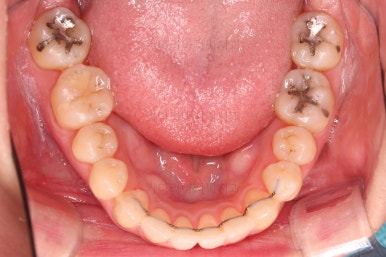

초진 시, 입안의 모습입니다.

위아래 앞니가 긴밀하게 겹침이 없는 약간의 개방교합(오픈바이트, Openbite) 경향이 보입니다.

개방교합을 개선하면서 교합을 맞춰주고요.

디테일한 중앙선이라던지, 안에서 끄집어낸 치아의 각도라던지 비롯해서 환자분이 원하시는 느낌을 반영해서 마무리를 합니다.